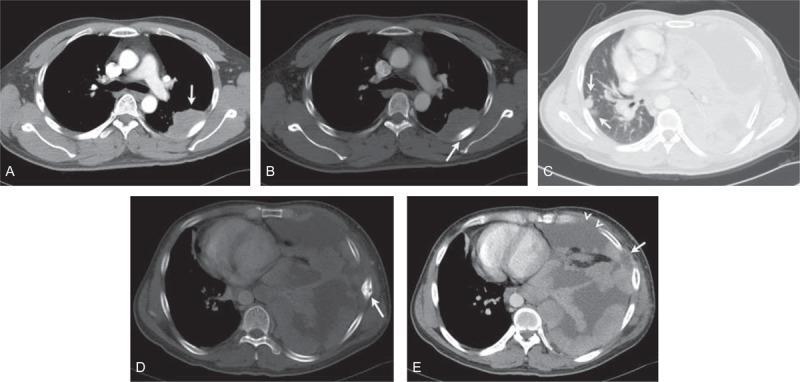

The aim of the study was to describe the imaging findings of Askin tumors on computed tomography (CT) and fluorine 18 fluorodeoxyglucose-positron emission tomography (FDG-PET/CT).Seventeen cases of Askin tumors confirmed by histopathology were retrospectively analyzed in terms of CT (17 cases) and FDG-PET/CT data (6 cases).Fifteen of the tumors were located in the chest wall and the other 2 were in the anterior middle mediastinum. Of the 15 chest wall cases, 13 demonstrated irregular, heterogeneous soft tissue masses with cystic degeneration and necrosis, and 2 demonstrated homogeneous soft tissue masses on unenhanced CT scans. Two mediastinal tumors demonstrated the irregular, heterogeneous soft tissue masses. Calcifications were found in 2 tumors. The tumors demonstrated heterogeneously enhancement in 16 cases and homogeneous enhancement in 1 case on contrast-enhanced scans. FDG-PET/CT images revealed increased metabolic activity in all 6 cases undergone FDG-PET/CT scan, and the lesion SUVmax ranged from 4.0 to 18.6. At initial diagnosis, CT and FDG-PET/CT scans revealed rib destruction in 9 cases, pleural effusion in 9 cases, and lung metastasis in 1 case. At follow-up, 12 cases showed recurrence and/or metastases, 4 cases showed improvement or remained stable, and 1 was lost to follow-up.In summary, CT and FDG-PET/CT images of Askin tumors showed heterogeneous soft tissue masses in the chest wall and the mediastinum, accompanied by rib destruction, pleural effusion, and increased FDG uptake. CT and FDG-PET/CT imaging play important roles in the diagnosis and follow-up of patients with Askin tumors.

本研究的目的是描述Askin肿瘤在计算机断层扫描(CT)和氟-18氟脱氧葡萄糖正电子发射断层扫描(FDG-PET/CT)上的影像学表现。对17例经组织病理学确诊的Askin肿瘤病例进行回顾性分析,分析其CT(17例)和FDG-PET/CT数据(6例)。15例肿瘤位于胸壁,另外2例位于前纵隔中部。在15例胸壁病例中,13例表现为不规则、不均匀的软组织肿块,伴有囊性变和坏死,2例在平扫CT上表现为均匀的软组织肿块。2例纵隔肿瘤表现为不规则、不均匀的软组织肿块。2例肿瘤发现有钙化。增强扫描时,16例肿瘤表现为不均匀强化,1例表现为均匀强化。FDG-PET/CT图像显示,所有6例行FDG-PET/CT扫描的病例代谢活性均增加,病变SUVmax范围为4.0至18.6。初诊时,CT和FDG-PET/CT扫描显示9例有肋骨破坏,9例有胸腔积液,1例有肺转移。随访时,12例出现复发和/或转移,4例病情改善或保持稳定,1例失访。总之,Askin肿瘤的CT和FDG-PET/CT图像显示胸壁和纵隔有不均匀的软组织肿块,伴有肋骨破坏、胸腔积液和FDG摄取增加。CT和FDG-PET/CT成像在Askin肿瘤患者的诊断和随访中发挥着重要作用。